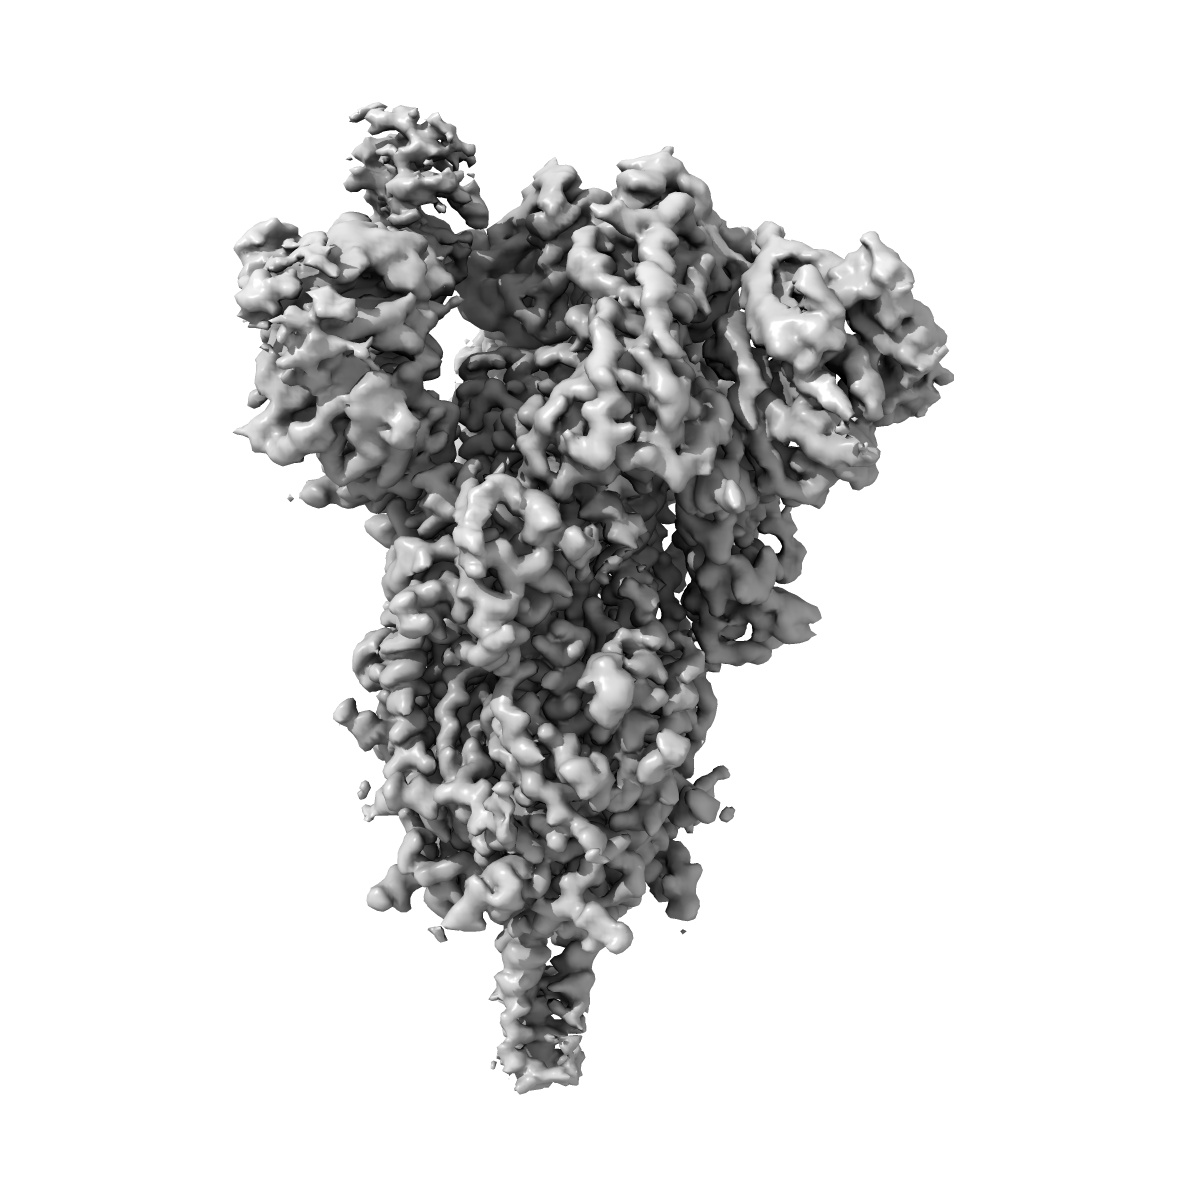

Single-particle

2.9 Å

Cryo-EM structure of SARS-CoV-2 S-Delta variant (B.1.617.2), one RBD-up conformation 4